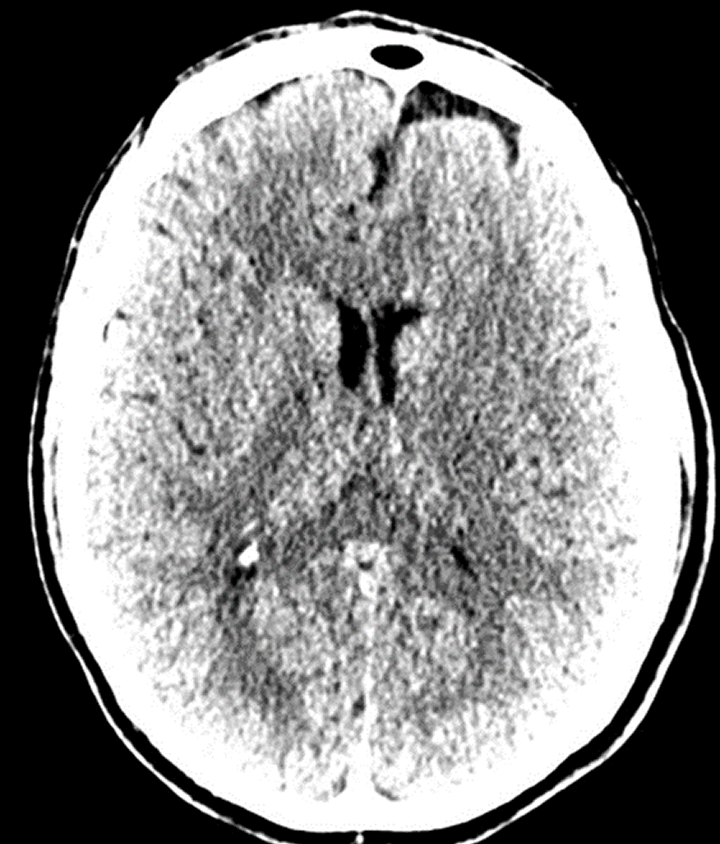

Before: "fuzzy" head CT

datascientists after

After: detailed images

Our V Star computer scientists wrote a module for 3D-Slicer allowing careful alignment and summation from 8 prior CT scans obtained over a course of several years. This improved image contrast resolution without loss of spatial resolution